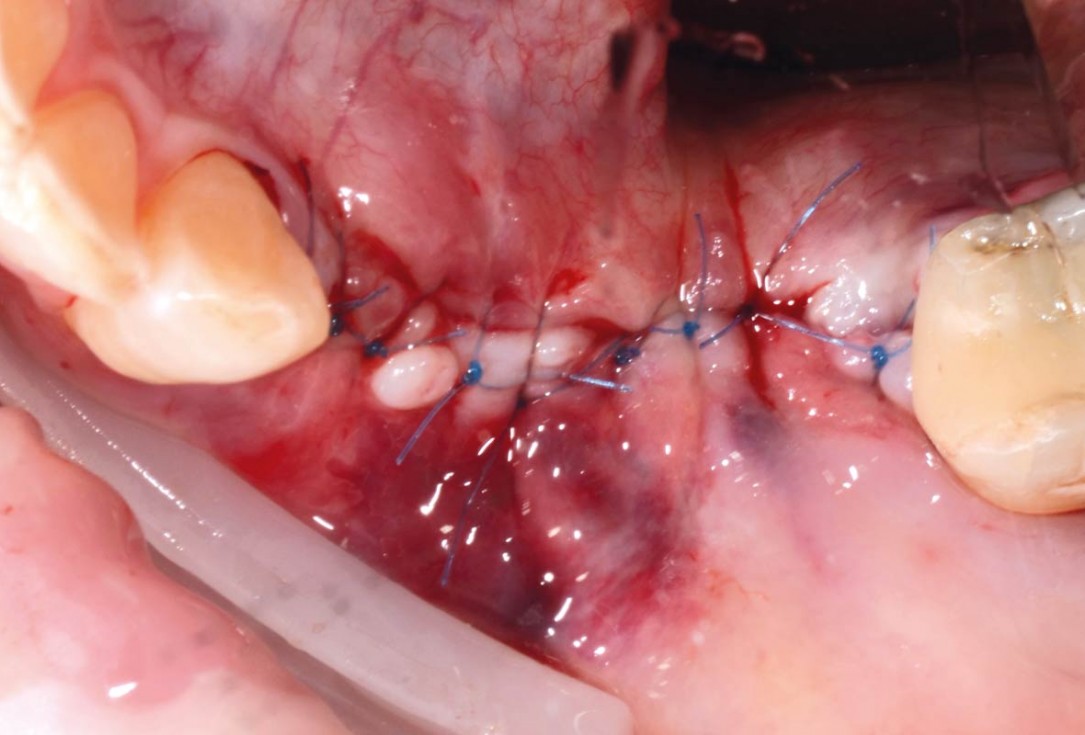

08/29 - Defect closure with non-absorbable PTFE suturesVertical bone augmentation and broadening of attached gingiva using cerabone®, permamem® and mucoderm® - Dr. R. Naimoli

19/29 - Flap closureVertical bone augmentation and broadening of attached gingiva using cerabone®, permamem® and mucoderm® - Dr. R. Naimoli